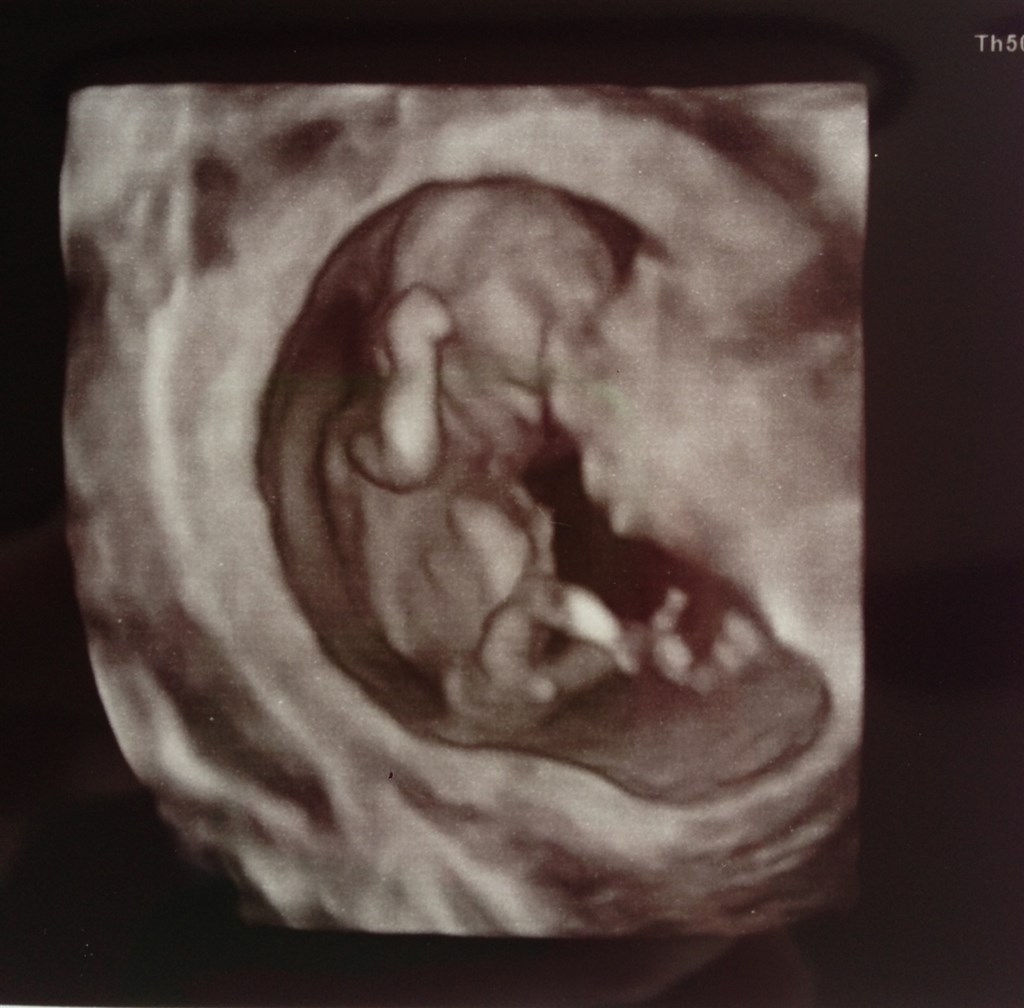

Og det andet billede

Vedhæftede fotos (klik for at se i fuld størrelse)